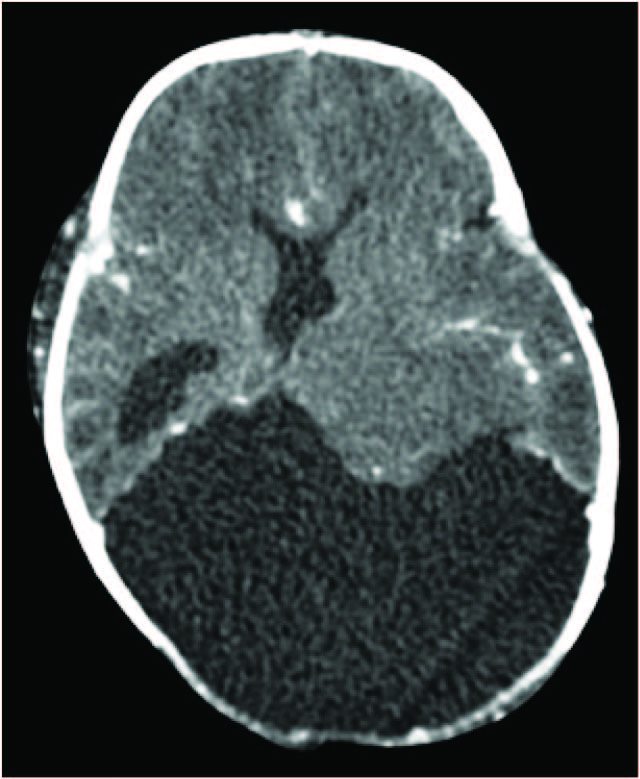

CT head showed a large well defined, hypo dense intracranial cystic lesion with attenuation value similar to CSF in bilateral posterior parietal and occipital regions. The lesion communicated with bilateral lateral ventricles and subarachnoid space. Bilateral lateral ventricles appeared dilated with thinning of over lying brain parenchyma. The lesion displaced the brain stem anteriorly and compressed cerebellum from superiorly. Widely open anterior and posterior fontanelle with small amount of brain parenchymal tissue seems to herniated from anterior fontanelle. Bilateral thalami appeared normal. On post contrast image cystic lesion was non enhancing without any solid component within. Provisional diagnosis of congenital porencephalic cyst was made. Then patient was referred to the higher center for further management [Table/Fig-1,2,3,4,5,6].

Axial Plain CT head shows large well defined, hypodense intracranial cystic lesion with attenuation value similar to CSF in bilateral posterior parietal and occipital regions. The lesion communicated with lateral ventricle and subarachnoid space. Widely open posterior fontanelle